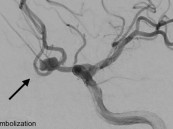

حقق مستشفى المانع بالأحساء إنجازًا طبيًا بنجاح تنفيذ أول إجراء من نوعه لإغلاق تمدد شرياني دماغي نازف بالقسطرة لمريض يبلغ من العمر 45 عامًا، جرى تحويله من مستشفى آخر إثر إصابته بنزيف حاد في الدماغ.وأُدخل المريض إلى وحدة العناية المركزة ...